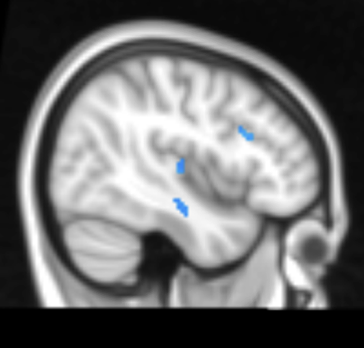

Here’s where things get more hopeful. Recent research into what happens to the brain after weight loss tells a more optimistic story. Following a structured weight loss intervention, activity decreased significantly in brain regions that are typically overactive in obesity – areas tied to food reward, taste processing, and decision-making around eating (figure 1). Critically, these changes didn’t show up after a 48-hour fast, meaning they weren’t just a side effect of short-term hunger. They appear to be genuine adaptations tied to actual reductions in body weight and fat mass. Leptin levels dropped alongside brain activity, suggesting the brain is recalibrating in response to a changed metabolic environment. [2]